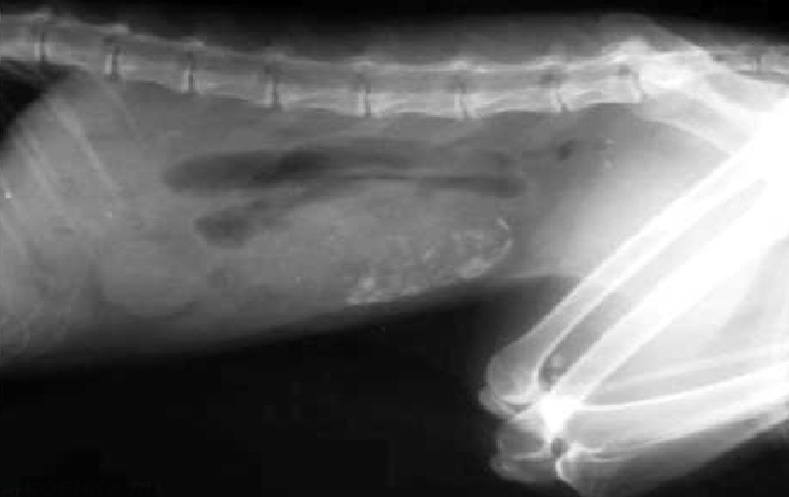

- Рентгенография – позволяет рассмотреть петли тонкого кишечника, располагающиеся в центральной зоне брюшной полости в двух проекциях – вентродорсальная и боковая. Аномальное расширение исследуемого материала сигнализирует о растяжении от постороннего предмета или от иных причин. На снимке можно обнаружить металлические вещи, кости, камни, стекло. Впрочем, не всегда инородные тела видны с помощью рентгенографии. Так, сложно обнаружить на снимке нитки, резиновые изделия, полиэтилен или тряпку. В этом случае применяют контрастную рентгенографию или другие способы исследования.

При первичном осмотре мы обнаружили умеренную абдоминальную болезненность и обезвоживание 3-4%. Общее состояние было удовлетворительным. Но на рентгенограммах были признаки нанизывания кишечника на линейное инородное тело.

Ваш ветеринар может порекомендовать рентген брюшной полости, чтобы лучше понять, что происходит в брюшной полости. Они будут искать инородное тело, а также обнаруживать изменения в газовой структуре кишечника (что указывает на закупорку).

Рекомендации теста могут включать: - Рентгенограммы брюшной полости (рентгеновские снимки) — важный тест. К сожалению, не все инородные материалы видны на первоначальном рентгеновском снимке. Иногда рекомендуется добавление красителя, такого как барий, чтобы определить наличие инородного тела или непроходимости желудка.

Рентгенограммы (рентгеновские снимки) были сделаны для оценки его живота.

Твердый объект располагался в кишечнике в каудальном левом квадранте брюшной полости.Поскольку он перекрывал толстую кишку, не сразу было очевидно, находится ли объект в тонком или в толстом кишечнике. Мы провели ультразвуковое исследование его брюшной полости и обнаружили объект в тонкой кишке, на полпути между желудком и толстой кишкой.